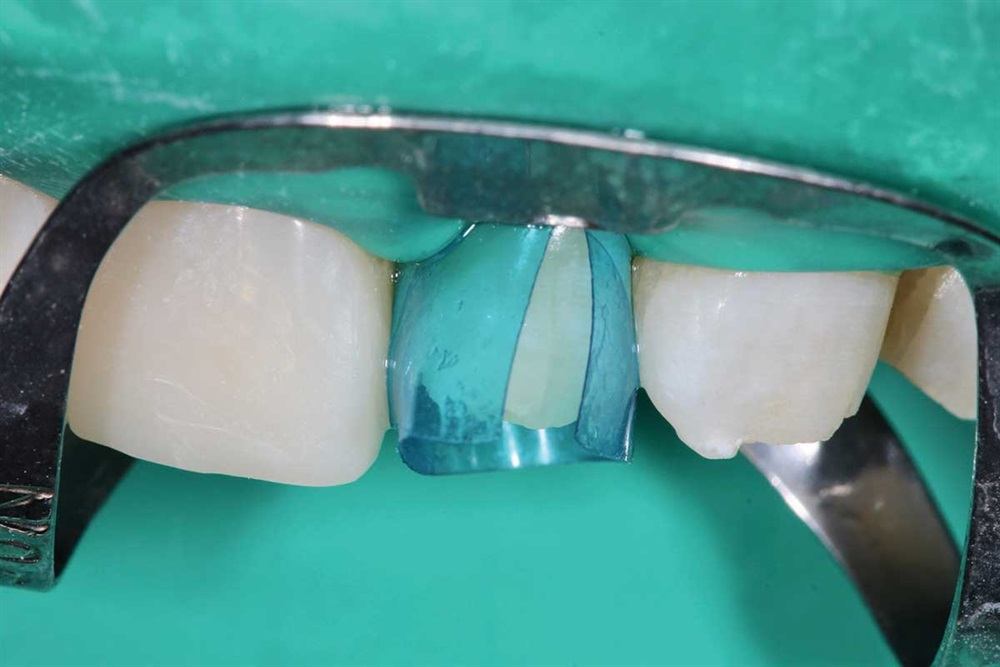

Show Your Work

Fig. 27: Starting the maxillary teeth with 90N, rubber dam and Premier Cure-Thru contoured matrix band. Incisal view.